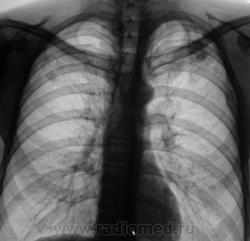

Через год, после проведенного "специфического" лечения.

Рентгенограмма.

Я бы остановилась на множественных туберкулемах s1-2 обоих легких,Туберкулемы не однородны.за счет уплотнения,пл очаги.фиброз.

Слева туберкулома и корень подтянут Справа-очаги отсева .Динамика типичная- лечим.лечим-а туберкуломе хоть бы хны!

Туберкулёма только в С1+2 слева, как дела давно минувших дней.  Произошла реактивация туберкулёзного процесса с развитием двустороннего очагового туберкулёза. Имеется положительная динамика в виду некоторого уплотнения очагов. Таково мое мнение.